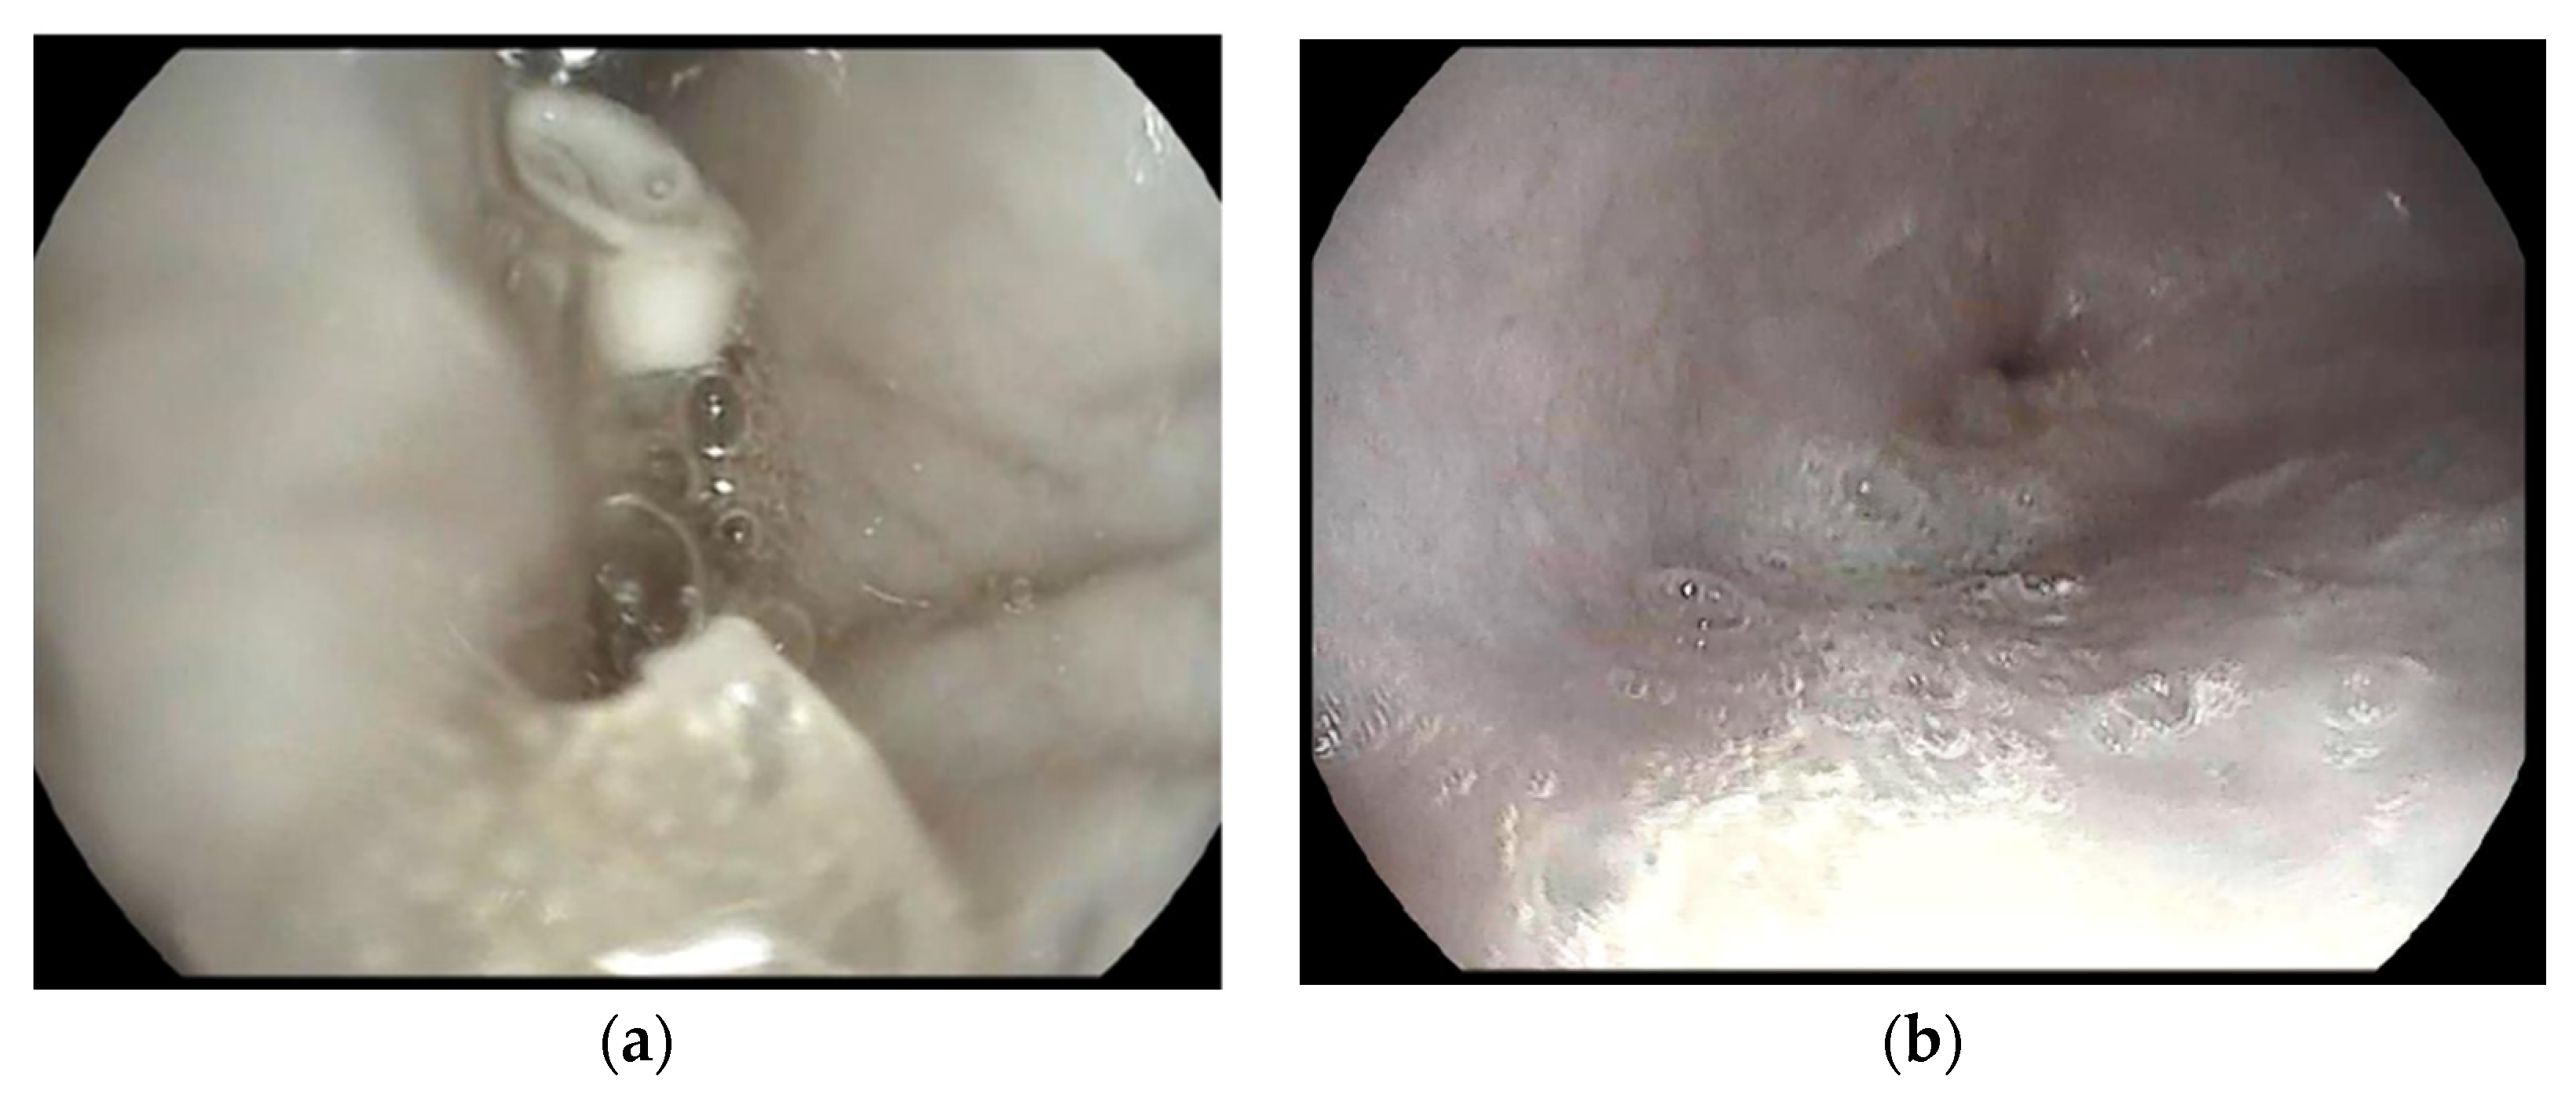

3.10. In Vivo Study